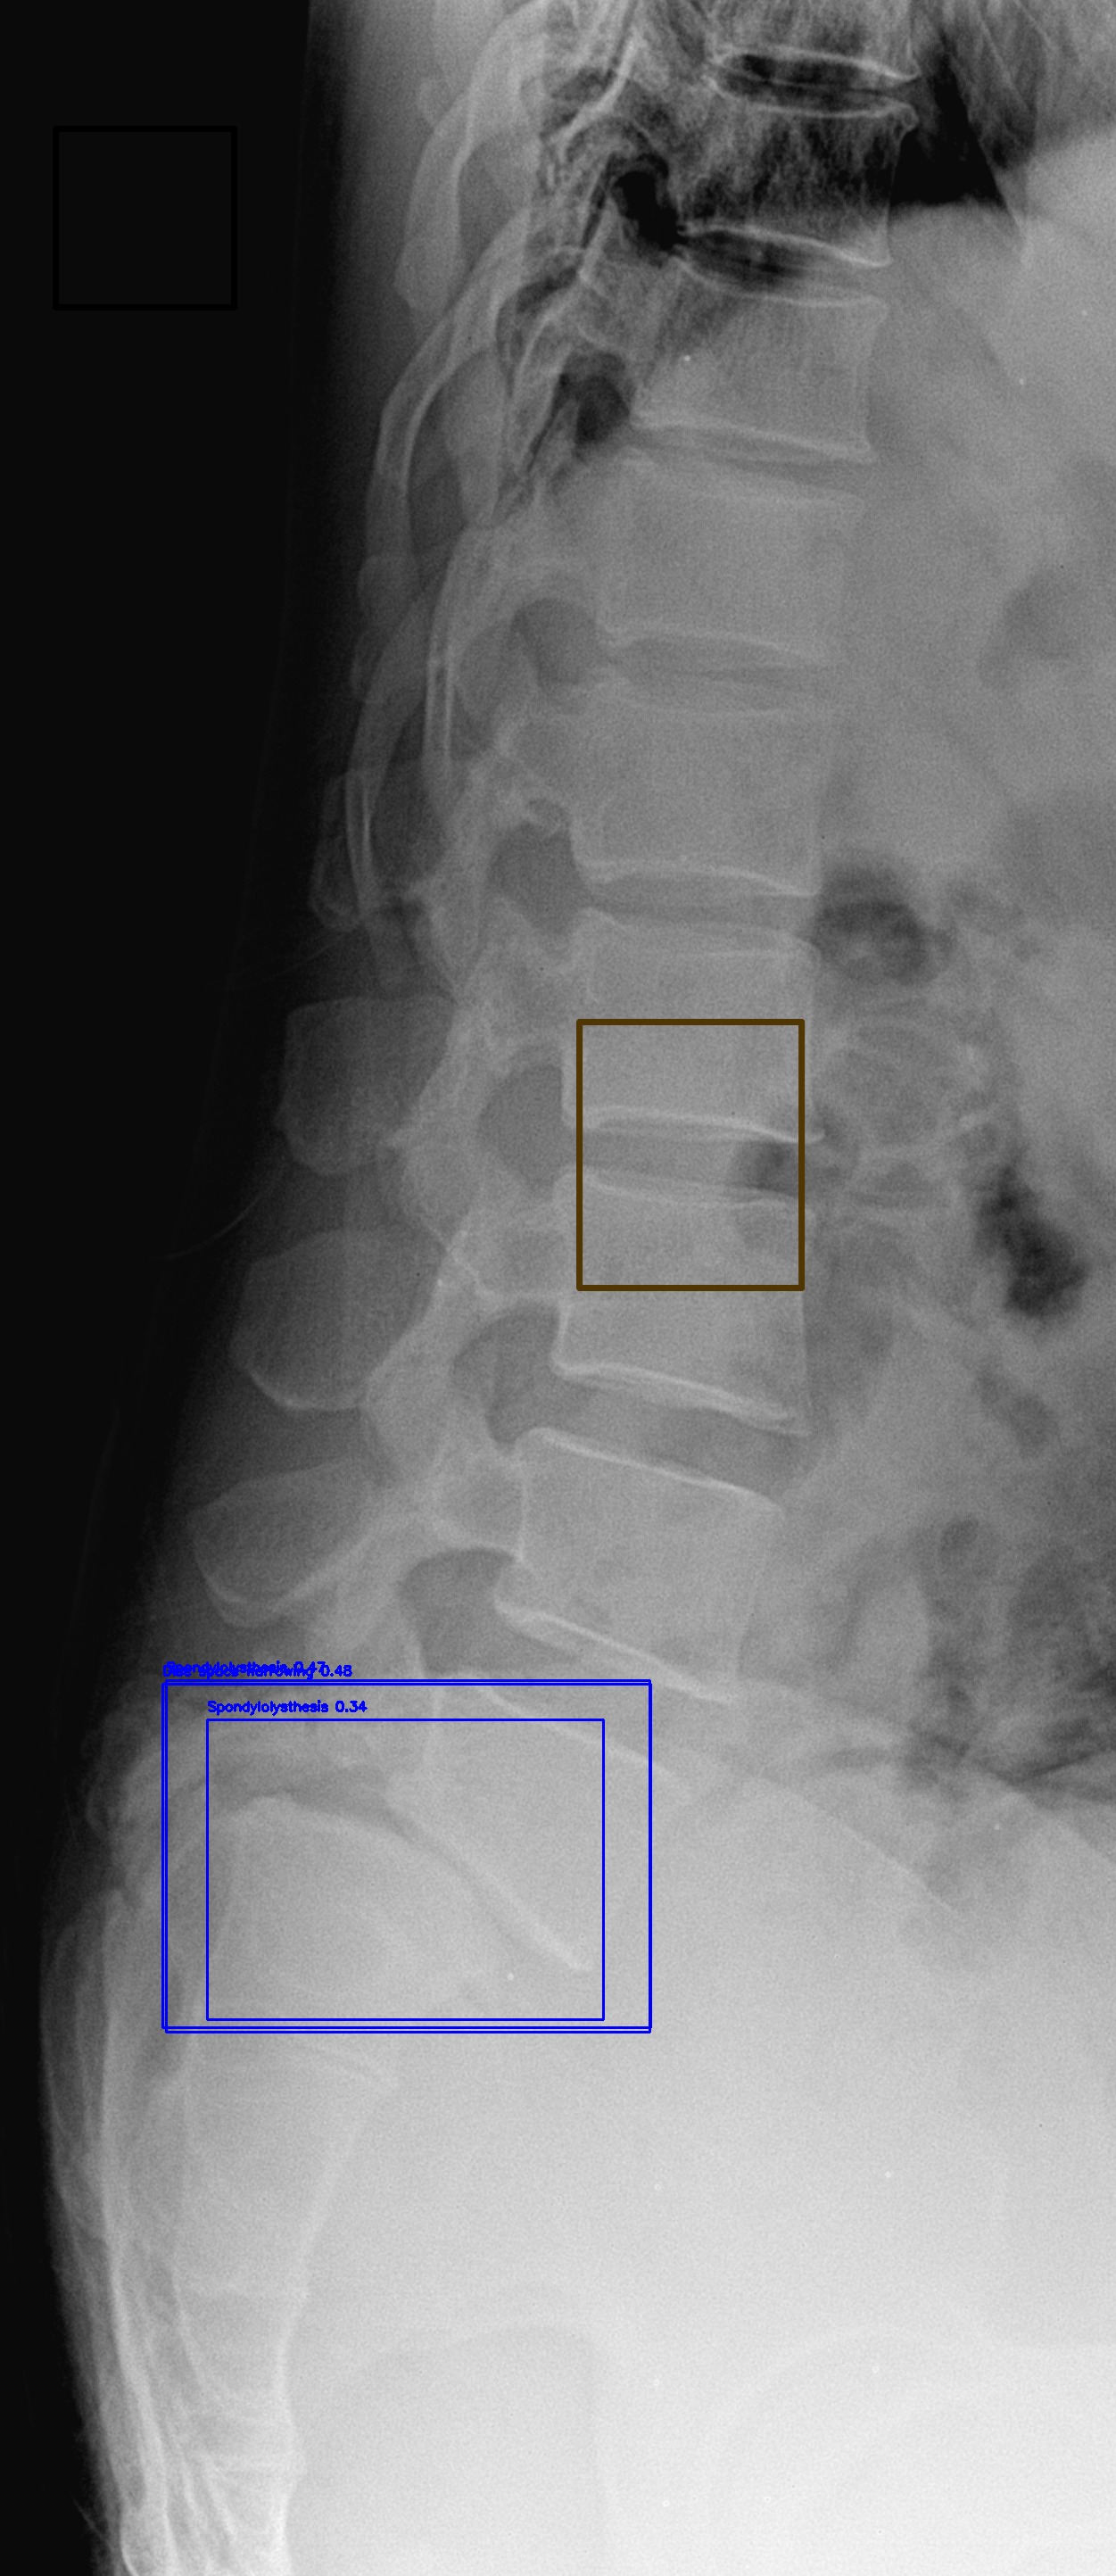

Spondylolisthesis

(c) Spondylolisthesis

Automated Lesion Detection and Localization: Visual demonstration of the cascaded DERNet-YOLO11 framework on VinDr-SpineXR benchmark images. The figure presents eight representative cases including seven pathological conditions with precise bounding-box localization: (a) Vertebral Collapse, (b) Osteophytes, (c) Spondylolisthesis, (d) Surgical Implants, (e) Disc Space Narrowing, (f) Foraminal Stenosis, (g) Other Lesions, alongside (h) a Normal spine radiograph for comparison. Each pathological case demonstrates the model's capability to accurately detect and spatially localize subtle lesions despite significant class imbalance (46.9:1 ratio), small object scales (often <1% of image area), and anatomical structure overlap. The localization boxes validate the clinical applicability of the integrated triage–localization pipeline.